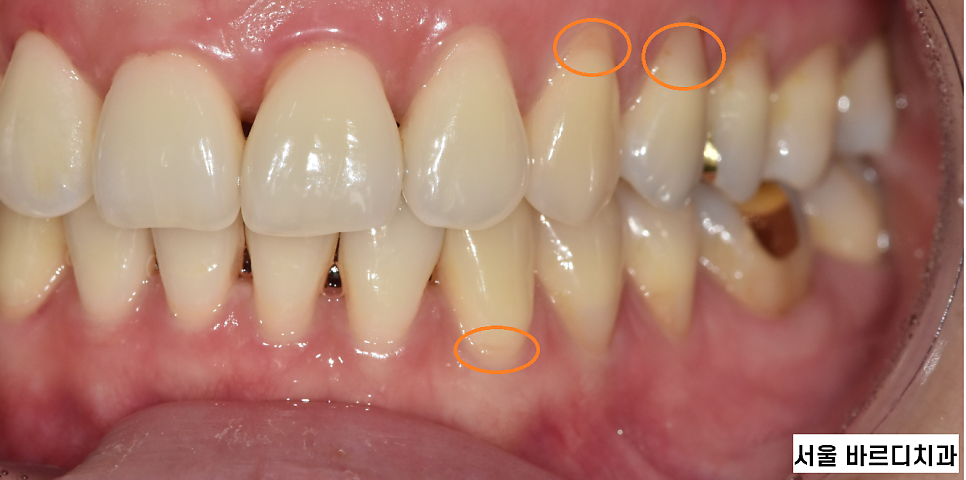

- 잇몸 퇴축

교정 치료로 인해 치아가 이동하면서 잇몸이 내려가고,

치아 뿌리가 노출되는 잇몸 퇴축이 발생할 수 있습니다.

치아 뿌리가 노출되면

차가운 물이 닿으면 시릴 수 있어요!

241209 치아 뿌리가 노출 되었어요!!

심한 경우 잇몸이 내려가면서 빈 공간이 생길 수 있는데

이를 "블랙 트라이앵글"이라 말합니다.

예방을 위해 교정 치료 전 잇몸 건강 상태를 점검하고

치료 중에는 주기적인 스케일링으로

잇몸이 퇴축되고 내려가는 것을 방지하여야합니다!